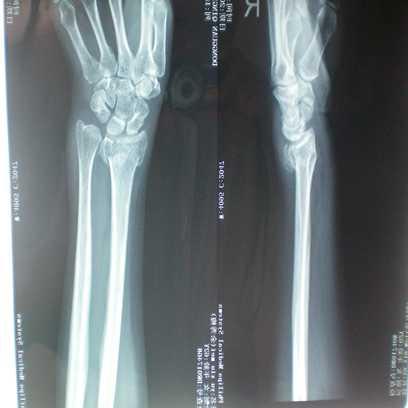

桡骨粉碎性骨折

手法正骨前

余**,女,55岁

患者不慎摔倒损伤右手,后经拍片示:右桡骨粉碎性骨折伴右桡尺关节半脱位,医院建议手术治疗,患者不想手术,想中医保守冶疗,后经朋友介绍来诊,经本门诊特色手法整骨及夹板固定,再次拍片示,骨折对位对线良好已达98%以上。